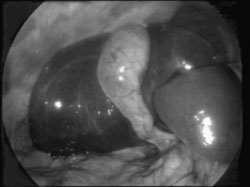

O fundo da vesícula é "laçado" com o

vesícula (Figuras 3 e 4).

| Figura 4 - O mesmo caso após a tração pelo "Lap-loop", mostrando a vesícula tracionada, o fígado rebatido, o pedículo vesicular e a via biliar principal. |